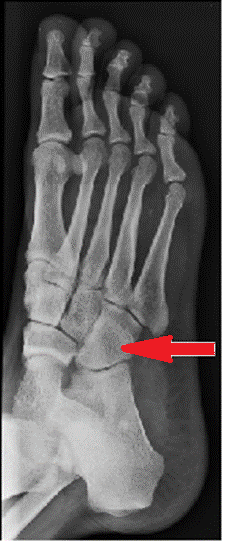

Wskaż przyczynę powstania artefaktu widocznego na obrazie MR.

Ilustracja do pytania 25

A. Wymiary obiektu przekroczyły pole widzenia.

B. Niejednorodność pola magnetycznego.

C. Nieprawidłowa kalibracja aparatu.

D. Błędny dobór cewki gradientowej.